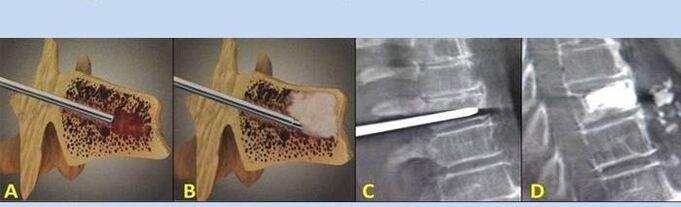

- Nucleoplasty– removal of the nucleus of the intervertebral disc.The operation relieves pressure on the nerve endings.

- Vertebroplasty with puncture– method of stabilization of the vertebrae.During the procedure, the doctor fills the cavities of the spine with bone cement.